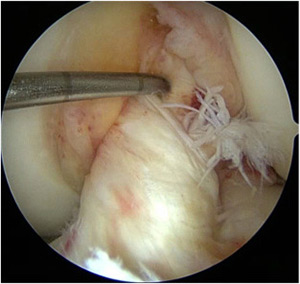

- Modified Lemaire Lateral Extra-Articular Tenodesis Using an Inlay Technique and All-Suture Knotless Anchor Fixation

- Primary Anterior Cruciate Ligament Repair: Current Concepts

- Arthroscopically Assisted Fixation of Terrible Triad Variant Injuries of the Elbow With Small-Bore Needle Arthroscopy

- Osteochondral Allograft Transplantation Of Posterior Femoral Condyle Lesions Utilizing An Open Posterior Approach To The Knee

- Modified Bosworth Technique for Medial Collateral Ligament Reconstruction of the Knee Using Semitendinosus Tendon Autograft

- Quadriceps Tendon Allograft for ACL Reconstruction With and Without a Bone Block

Photo Gallery